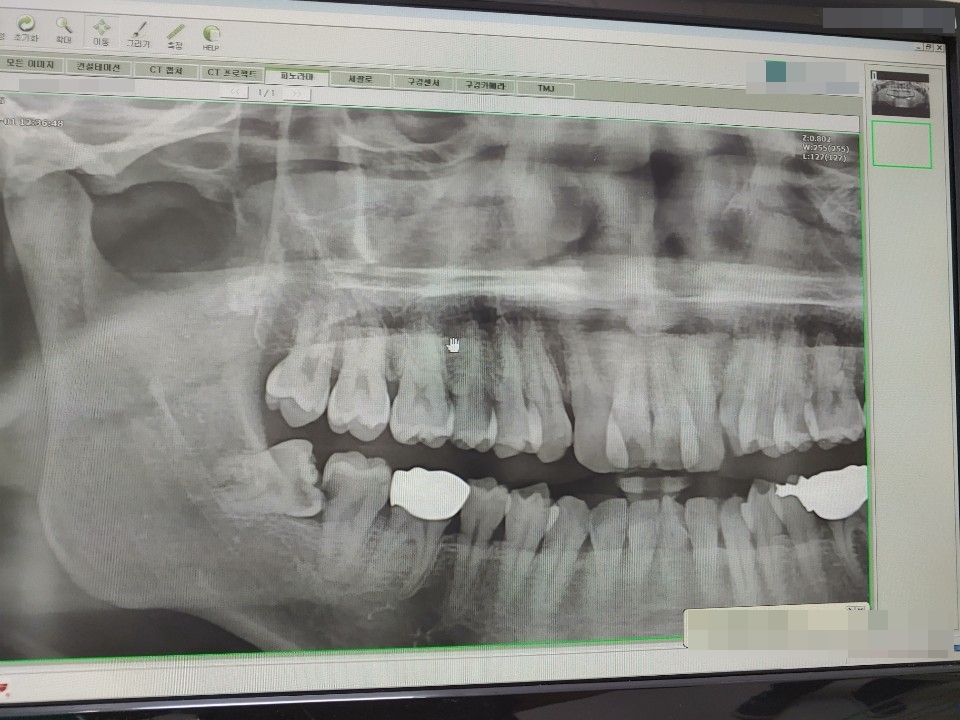

2. 엑스레이 사진

이게 저의 엑스레이 사진인데요. 딱 봐도 상태가 안 좋다는 것을 일반인이 봐도 알 수가 있습니다. 이미 옆에 어금니는 충치로 썩었으며, 반대편도 이렇게 있다고 생각하시면 됩니다.

저는 위에 있는 사랑니까지 총 4개가 있었지만 아래에 있는 2개만 빼기로 했습니다. 사랑니를 한 번에 빼게 되면 음식 먹는 게 불편하기 때문에 한쪽을 빼고 아물었을 때 다른 한쪽을 빼게 됩니다.

만약 위에도 빼게 된다면 같은 쪽으로는 2개를 빼도 되지만 아래를 한번에, 또는 위에를 한 번에 빼는 경우는 없습니다.